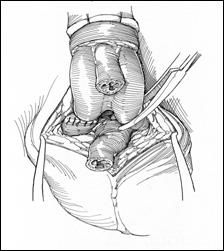

4. Amputatia partiala de penis

Radicalitatea oncologica prin amputatia partiala este asigurata prin realizarea marginii de siguranta de 2 cm. Dupa izolarea leziunii cu o manusa chirurgicala se va aplica un tourniquet la baza penisului.

Tegumentul se incizeaza circular. Corpii cavernosi sectioneaza pana la uretra. Sunt ligaturate vasele dorsale. Uretra este disecata astfel incat sa se obtina 1 cm distal fata de limita de rezectie a corpilor cavernosi. Nu se face rabat oncologic la disectia uretrei.

Hemostaza se realizeaza la nivelul corpilor cavernosi cu fire separate aproximand marginile fasciei Buck. Se va indeparta tourniquet-ul. Uretra este spatulata pe fata dorsala pentru a preveni stenoza de meat. Se anastomozeaza tegumentul la uretra cu suturi absorbabile 3/0 sau 4/0.

Tegumentul redundant este aproximat dorsal pentru a completa inchiderea plagii. Cateterul utretro-vezical este mentinut pentru minim 24 h.

Cand bontul penian este prea scurt pentru a directiona jetul urinar se poate obtine o lungire suplimentara a bontului prin sectionarea ligamentului suspensor al penisului, sectionarea muschilor ischiocavernosi sau disectia partiala a corpilor cavernosi de ramurile pubiene.

a. b.

Figura 17. Amputatia partiala de penis. a) schema anatomica; b) imagine intraoperatorie.